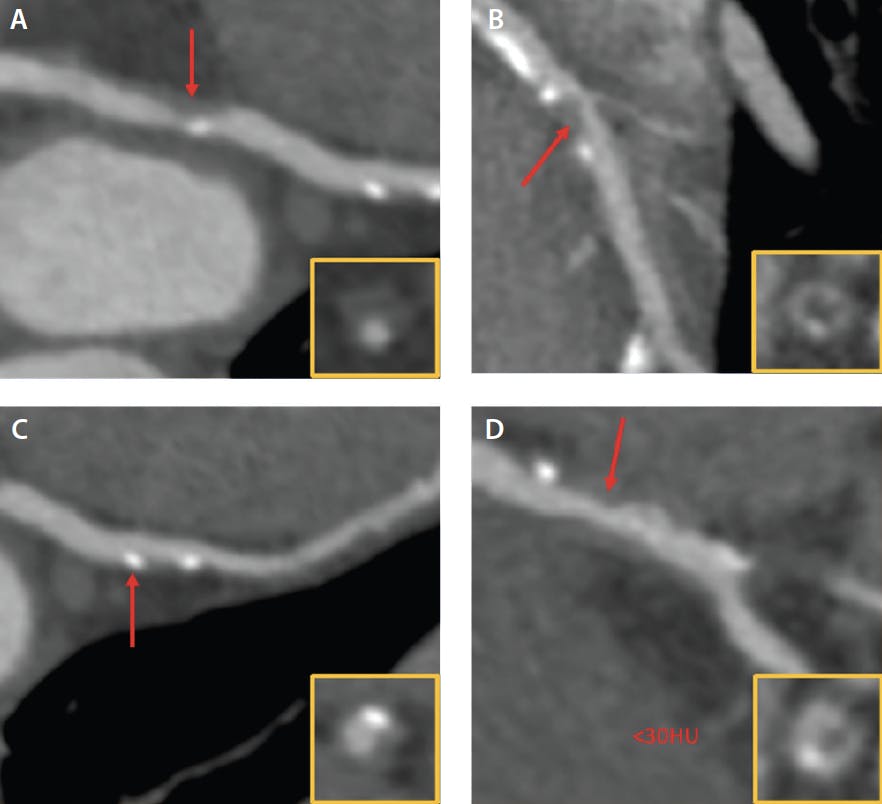

Plaques can be classified broadly based on their dense calcium components, high-risk features known as vulnerable plaques, or the American Heart Association histopathology classification system. High-risk plaques identified on coronary CTA are known to demonstrate features such as low-attenuation plaque, positive remodeling, napkin-ring sign, and spotty calcification (Figure 2). While it is hypothesized that vulnerable plaques are responsible for most myocardial infarctions, not all plaques with such features lead to an acute event. The atherosclerotic plaque type most commonly associated with culprit lesions is a thin-cap fibroatheroma (< 65 μm), which is characterized by a large necrotic or lipid core separated from the vessel lumen by a thin layer of epithelial cells. These observations suggest that not only the presence but also the evolution and progression of high-risk plaque pose a greater cardiovascular risk.

Figure 2. Coronary atherosclerotic vulnerable plaque features as seen on coronary CTA. Positive remodeling (A), napkin-ring sign (B), spotty calcification (C), and low-attenuation plaque (D).